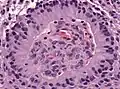

Периваскулярные псевдорозетки в эпиндимоме

Эпендимальные псевдорозетки вокруг пролиферирующего эндотелия при анапластической эпендимоме